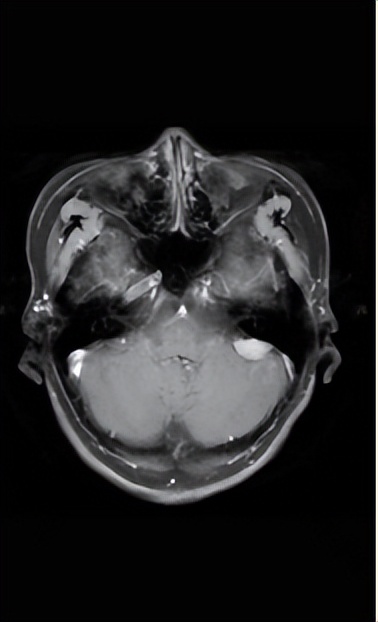

了解张先生的病情后,完善相关检查。查体:左侧耳鸣,但听力仍与右侧保持一致,右侧无明显面瘫情况;眼球活动灵敏;吞咽无呛咳,耸肩有力,伸舌居中。头颅MRI(核磁)(图1)显示左侧桥小脑角区有一异常信号,考虑是脑膜瘤。

图1所示:左侧桥小脑角区有一异常信号